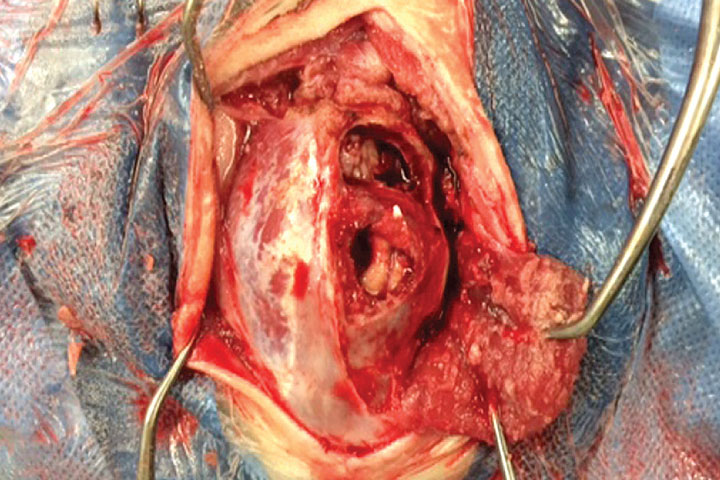

Multilobular Osteochondrosarcoma

These are slow growing tumours that arise from the skull but can cause severe compression of the brain. Although not primary tumours, they may not be noticed until neurological signs appear. Surgery can be very successful in these cases.